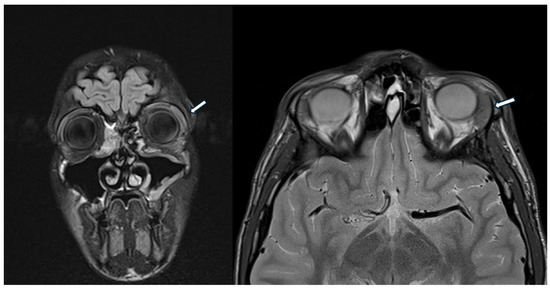

A 12-year-old Caucasian girl was admitted to the emergency department for a prolonged and fluctuating asymptomatic swelling and redness of her left upper eyelid, which started about six months earlier. The girl was initially treated with local antibiotics, and then, after about two months, she was hospitalized. A computed tomography (CT) scan detected signs of palpebral cellulitis, maxillary sinusitis, and lytic lesions on the lateral side of the orbit and the left frontal bone (Figure 1).

Figure 1.

Multiple, partially confluent, osteolithic lesions in zygomatic and frontal bones. Paranasal sinus involvement.